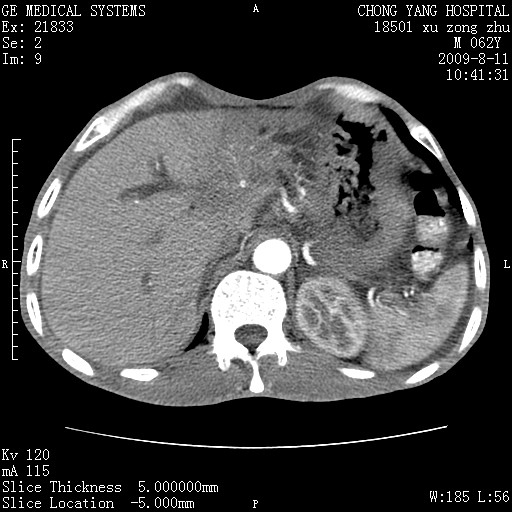

以下是引用杀毒软件在2009-8-11 16:35:00的发言:[br]肝内胆管扩张局限于左叶,胆管内有结石伴肝外胆管结石,胆管壁增厚呈弥漫性并发腹腔积液,胰腺边界模糊。[br][br]考虑---胆总管及肝内胆管结石继发胆管炎及胰腺炎,左肾下极囊肿,腹水。

以下是引用zjzjr在2009-8-11 17:35:00的发言:[br]肝内胆管扩张局限于左叶,胆管内有结石伴肝外胆管结石,胆管壁增厚呈弥漫性并发腹腔积液。[br][br]考虑---胆总管及肝内胆管结石继发胆管炎,左肾下极囊肿,腹水。